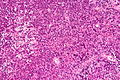

| Glioblastoma (WHO grade IV) | glial processes (esp. on smear), nuclear atypia (typical size var. ~3x, irreg. nuc. membrane, hyperchromasia), no Rosenthal fibres in the core of the lesion †, microvascular proliferation or necrosis | often enhancing (suggests high grade), usu. supratentorial, usu. white matter | usu. old, occ. young | very common, esp. glioblastoma | IDH-1+/-, GFAP+ | |

Images

Glioblastoma: